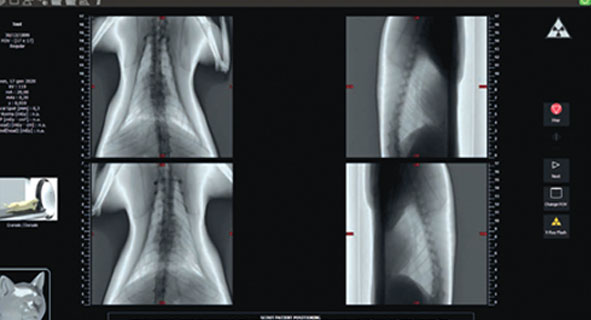

Широкий диапазон полей зрения, от 6×6 см до 21×19 см, гарантирует гибкость для любых диагностических задач, а 360-градусное сканирование отображает весь объём за один оборот. Технология SafeBeam™ автоматически регулирует дозу, а режим ECO Scan оптимизирует облучение.